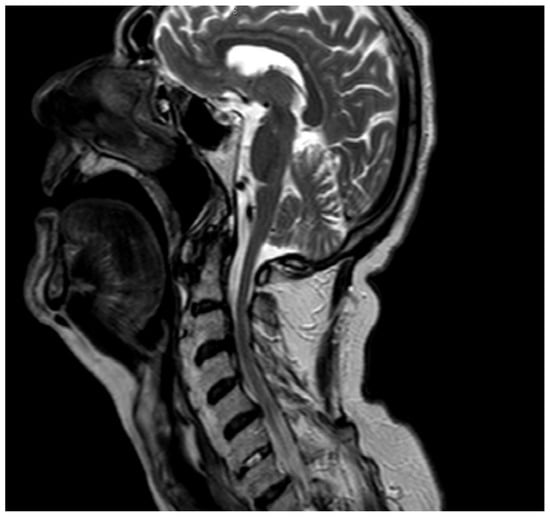

We performed a lateral–cervical spinal X-ray, a CT scan (Figure 2), and MRI (Figure 3) of the head, neck, and chest, which demonstrated anterior osteophytosis resulting in the compression of the esophagus between levels C2 and C5 and widespread axial spondylarthrosis. We also performed an esophago-gastric endoscopy, which showed a normal and undamaged esophagus, with whitish-pink cardiac mucosa and no motility disorders (Figure 4); in addition, the lumen appeared to present an ab extrinsic compression at its proximal tract. Given the absence of upper digestive endoscopy abnormalities, we initiated a logopedic and postural rehabilitative treatment.

Figure 2. MRI showing diffuse spondyloarthrosis and osteophytes corresponding to the C2–C5 tract with a narrowing of the pharyngolaryngeal lumen.